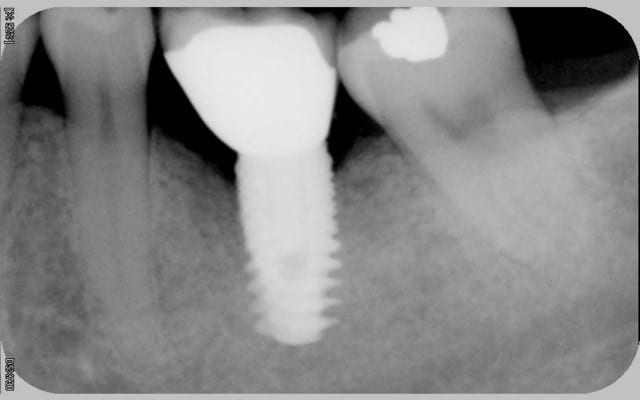

16/06/2010 à 16h05

comme promis

voici les cas vus ce mardi (il me manquait encore 10 patients: sur les 5 autres, tout est ok)

ps: la carie et le tartre sur la 7 ont été traités